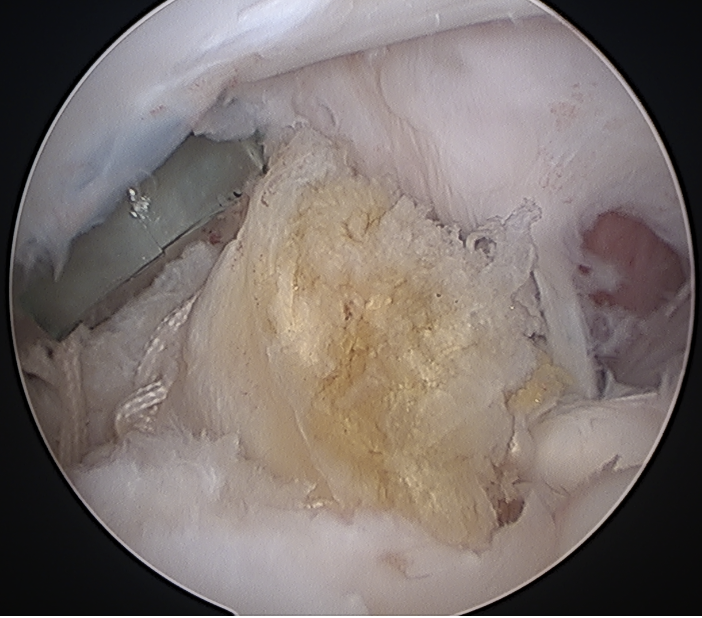

Tendonopathy

Tearing > 50% / thickening: Tenotomy / tenodesis

- tag biceps tendon with high strength suture and release

Tag biceps and release